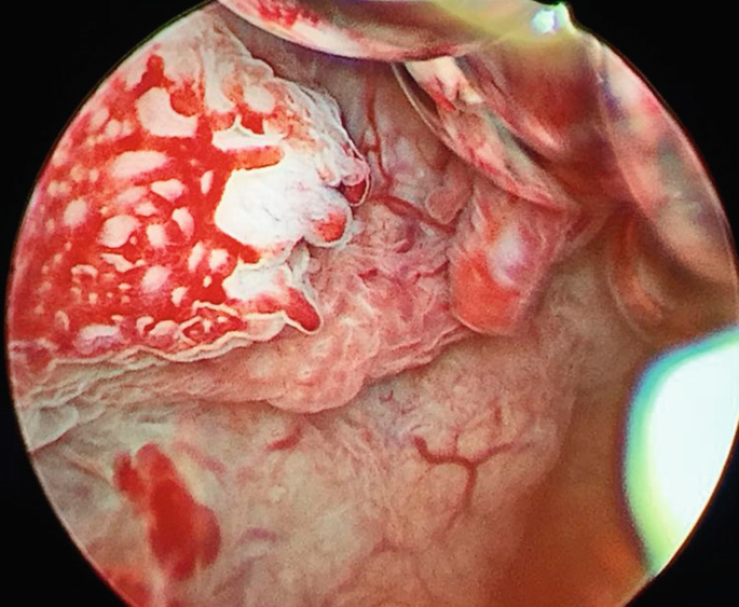

- Крок 3. Гістероскопія з прицільною біопсією/резекцією. Тонку камеру (гістероскоп) вводять через шийку матки в порожнину і бачать усе зсередини на екрані. За потреби одразу видаляють поліпи, підозрілі ділянки («шевінг», гістерорезектоскопія). У більшості випадків процедура проводиться під короткою седацією, пацієнтка не відчуває болю, а додому повертається того ж дня.